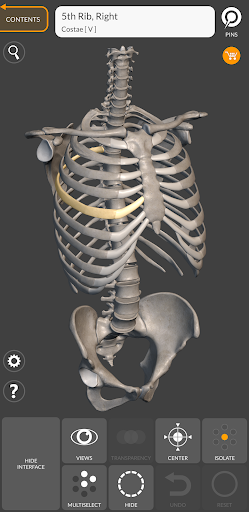

Mỗi xương của bộ xương người đã được tái tạo ở dạng 3D, bạn có thể xoay và phóng to từng mô hình và quan sát chi tiết từ mọi góc độ.

Bằng cách chọn mô hình hoặc ghim, bạn sẽ được hiển thị các thuật ngữ liên quan đến bất kỳ bộ phận giải phẫu cụ thể nào, bạn có thể chọn từ 12 ngôn ngữ và hiển thị các thuật ngữ bằng hai ngôn ngữ cùng lúc.

HÌNH GIẢI PHẪU 3D CÓ ĐỘ CHI TIẾT CAO

• Hệ thống xương

• Mô hình 3D chính xác

• Bề mặt của bộ xương có kết cấu độ phân giải cao lên đến 4K

• Xoay và Phóng to mọi mô hình trong không gian 3D

• Phân chia theo vùng để có hình ảnh rõ ràng và trực tiếp về từng cấu trúc

• Khả năng ẩn mọi xương

• Ghim tương tác cho phép trực quan hóa thuật ngữ liên quan đến mọi chi tiết giải phẫu